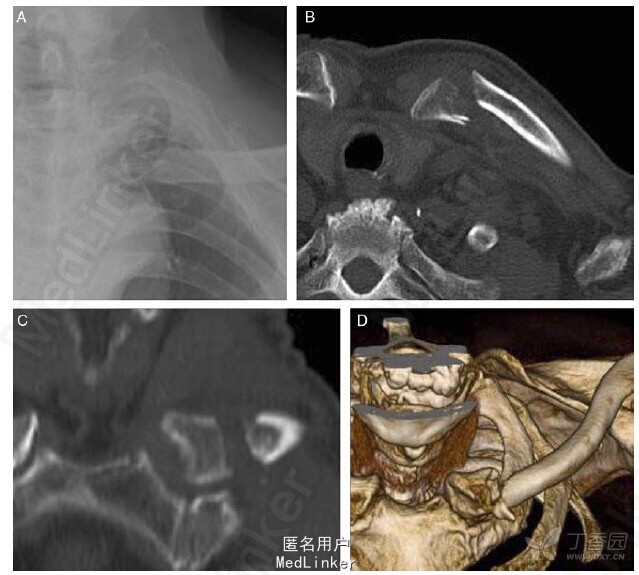

86 岁男性,摔倒后出现左胸锁关节疼痛,查体发现锁骨内侧肿胀和有明显的触痛。X 线和 CT 显示锁骨近端内侧发生移位性骨折(图 1)。入院后予吊带固定行保守治疗,但患者左胸锁关节处仍有疼痛和不能完成正常日常活动。因此,在受伤后第 10 天行手术治疗锁骨内侧骨折。

图 1:X 线(A)和 CT(B)显示锁骨近端内侧发生移位性骨折